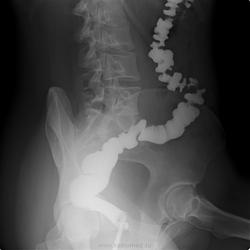

Возможно, есть изменения по-типу болезни Гирсшрунга, но неубедительно. Купол слепой кишки как бы кисетообразно подтянут по медиальному контуру, возможно есть поражение баугиниевой заслонки. Попробуйте провести энтерографию.

Никакой значимой патологии на представленных снимаках четко не определяется. То, что указано стрелками - м.б. просто спазм, м.б. и изъязвление, но не очень доказательно.

Рентгенограммы отличные, завидую (ах какая..., мне б такую). Но не люблю я это исследование, особенно в плане выискивания причин всяческих запоров. Вот и тут, я бы кроме нормы(в плане органики) ничего бы не нашел.

на мой взгляд не все изгибы разведены (может не все снимки представлены), нет тугого наполнения кишки, большая часть снимков с двойным контрастированием, да и без скопии сложно оценивать изменения указанные стрелками. а в целом без явных стойких сужений и дефектов наполнения.